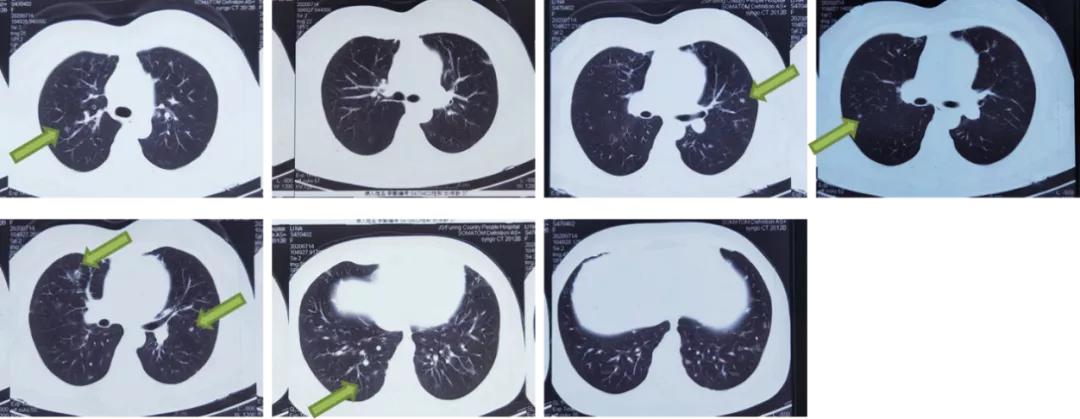

同日,行胸部CT显示:两肺多发结节、絮状影,性质待定,较8月27日(影像)片病灶增多、增大;纵隔、双侧腋窝小淋巴结;两肺局部少许炎症。

图6:胸部CT(2020.11.02)

胸部CT平扫+增强三维:1、双肺多发结节,突出病灶位于右肺下叶外基底段和左肺下叶前基底段。2、纵隔淋巴结肿大。3、肝脏钙化灶。4、右肾结石。5、脾大。双肺多发实性结节、玻璃结节,最大者位于右肺下叶外基底段(IM177),长径约1.7cm,边缘浅分叶,周围多发毛刺,内见含气支气管影。纵隔内可见数枚肿大的淋巴结。心脏大小未见明显异常,心包未见明显积液。双侧胸腔未见积液,胸膜未见增厚。肝内斑点状致密影,右肾结节状致密影,脾脏体积增大。

图7:胸部CT平扫+增强三维(2020/11/5)